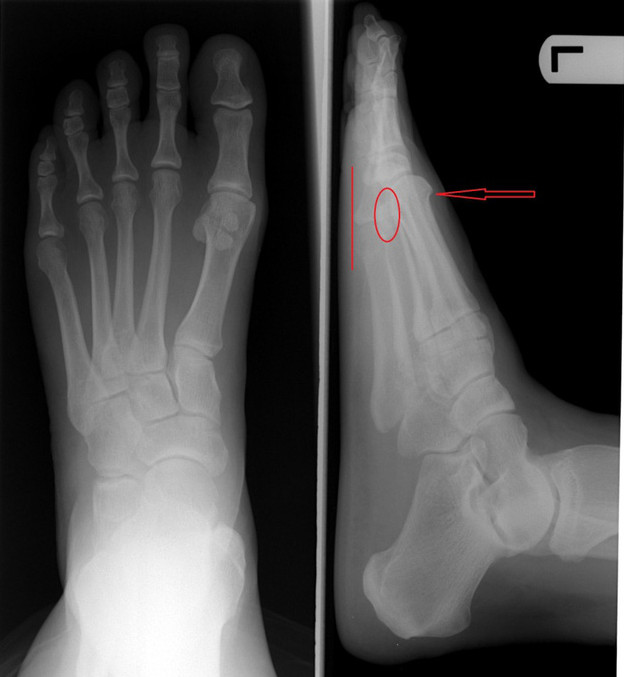

Trong ảnh chụp X-quanh, khi ngón trỏ dài hơn thì phần xương ngón chân cái cũng bị ép và cong sát vào với nó.

Khi đi bộ hoặc đứng phần cơ của các ngón chân khác trong bàn chân thường có xu hướng đổ về phía trước khiến nạn nhân của "bàn chân Hy Lạp" dễ bị đau đầu gối, hông và lưng dưới.